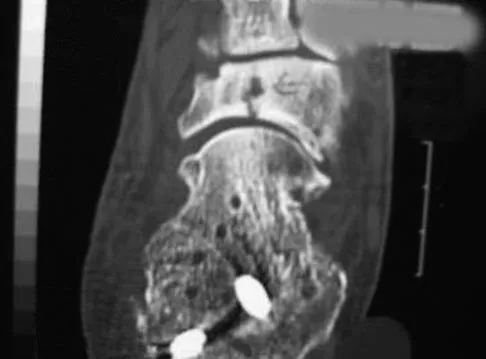

A 25-year-old woman has significant pain and swelling in her left ankle after falling off her bicycle. Examination reveals that she is neurovascularly intact. Radiographs are shown in Figures 33a through 33c. What is the next most appropriate step in management?